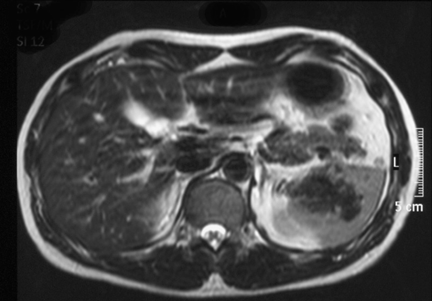

A 38-year-old man without any symptoms was found to have a splenic mass on routine medical examination. Physical examination found nothing remarkable. Laboratory test results were within normal limits. Tumor marker levels were not elevated (CEA: 1 ng/ml, AFP: 2 ng/ml, CA19-9: 2 ng/ml). Upper gastrointestinal (GI) series revealed extrinsic compression of the upper body of the stomach (Figure 1). An abdominal computed tomography (CT) scan revealed a 5-cm tumor and progressive delayed enhancement in the hilus of the spleen (Figure 2). Abdominal magnetic resonance imaging (MRI) revealed that the tumor was isointense on a T1-weighted image and hypointense on a T2-weighted image (Figure 3). The findings were confirmed by abdominal ultrasonography and we subsequently followed the patient by clinical and radiological examination. CT scan showed that the tumor was not enlarged four months after the initial presentation. It was thought that there was little possibility of malignancy, but on patient's request laparoscopic splenectomy was performed for diagnosis.

Figure 3: T2-weighted MRI revealed hypointensity of the tumor.